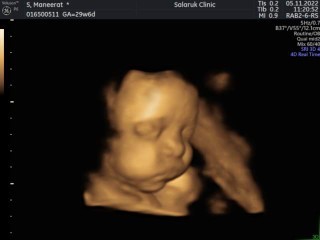

Đọc thêmท้องแรก ค่ะ ลูกสาว กำหนด 15/1/66 ไปซาวด์ล่าสุดตอน 29+6w นน.น้อง 1813 กรัม แม่เพิ่มมา 8 กิโล ตรวจน้ำตาลผ่านฉลุยค่ะ อาทิตย์หน้าคุณหมอนัดที่ 33+2w ลุ้นว่าแม่จะขึ้นกี่โล ลูกขึ้นอีกเท่าไหร่จ้า อาการแม่ตอนนี้ ปวดขาหนีบบ้างบางวัน แต่อึดอัดทุกวัน 😍😍